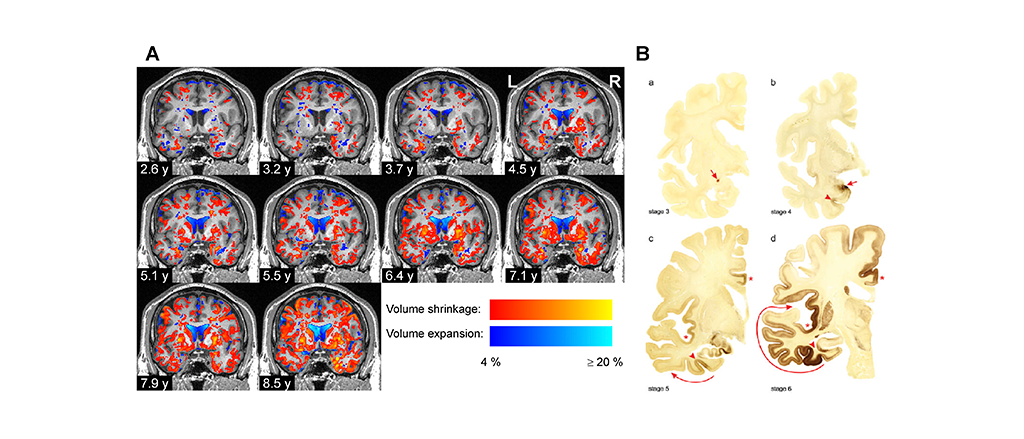

Progressive volume atrophy in Parkinson's disease.

At the beginning of the study, the team found that the volumes of several brain regions were smaller in the Parkinson’s disease patients than in the control group, whereas some regions were enlarged in the brains of patients, presumably because of compensatory effects. Over time, the difference between the groups became increasingly widespread and pronounced: The brain volumes of the Parkinson’s disease patients declined almost twice as quickly as those of the control group, particularly in the grey matter. Mostly affected by this volume decrease were the temporal and occipital lobes, neighbouring parts of the inferior parietal lobe and ventral parts of the frontal lobe.

The team analysed in detail which parts of the brain changed over time using neuroanatomical atlases, primarily the Julich Brain Atlas, which is openly accessible on EBRAINS. This detailed anatomical analysis revealed a very specific regional pattern of volume changes in the Parkinson’s disease patients that was different from healthy aging. The researchers found that the volume decreases of cortical areas, amygdala and basal forebrain in Parkinson’s patients were correlated with the worsening of clinical symptoms.

The specific pattern of regional volume decreases that they revealed coincided with the stage scheme of Parkinson’s disease proposed by Heiko Braak in 2003. Braak and colleagues had analysed 168 postmortem brains for the presence of aggregates form by misfolded alpha-synuclein proteins and postulated progressive propagation of the disease in six stages starting at the lower brain stem nuclei and olfactory bulb and progressing via the midbrain towards the prefrontal and premotor cortices.